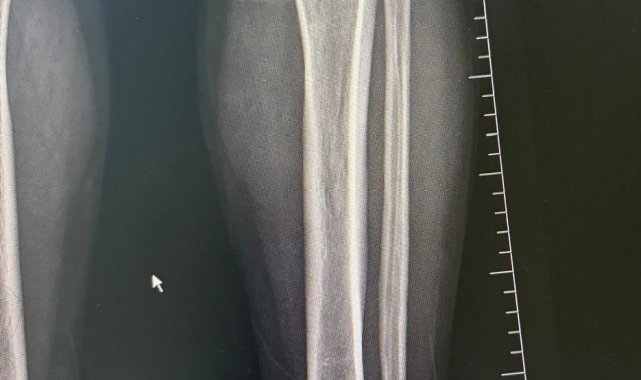

Ameliyat aşamasının ardından gerçekleşen süreci tek tek dile getiren Ortopedi ve Travmatoloji Uzmanı Prof. Dr. Mahmut Argün, "Hastamız 1.58 boyunda olması nedeniyle sürekli boyunun kısalığından dolayı hem fiziksel hem de bedensel rahatsızlıkların olduğunu dile getirdi. Israrla boyunun uzatılmasını bizden talep eden hasta 2 aşamalı olunması gereken muayeneyi 1 aşamalı olmasını istedi. Sol tarafından başlayarak hem femur hem de tibia 5 ila 6 santimetre arasında uzatmayı planladık. Hastamızı ameliyata alıp bu işlemleri gerçekleştirdik. Hasta şuanda uzatma işlemlerinin yapılabilmesi için malzeme yerleştirme aşamasını gerçekleştirdik. Ameliyattan 10 gün sonra uzatma işlemlerini başlayacağız. Uzatma işlemleri yaklaşık 60 gün sürecek. Uzatma işlem süreci geçtikten sonra işlemi durdurup kaynaması için 2-3 ay bekleyeceğiz. Ardından ise hastanın üzerinden malzemeleri yaklaşık 150-200 gün arasında çıkaracağız. Bu tarz işlemler meşakkatli ve özen isteyen ameliyatlar" diye konuştu.

Uzama sürecinde her gün 1 milimetre olmak üzere kurulan mekanizmanın başladığını dile getiren Ortopedi ve Travmatoloji Uzmanı Op. Dr. Necip Özateş, "Her gün 1 milimetre olmak üzere, üzerindeki mekanizma üzerinden hem uyruk kemiği hem kaval kemiği uzatılmaya başlıyor. Hem bu şekilde kemik uzaması hem de bu esnada kemik kaynaması aynı anda olduğu için daha kontrollü bir işlem oluyor. Hedef uzunluğa ulaştığımızda uzatma işlemini sonlandırıyoruz. Sonrasında da kemiğin kaynaması sürecine geçiyoruz" dedi.